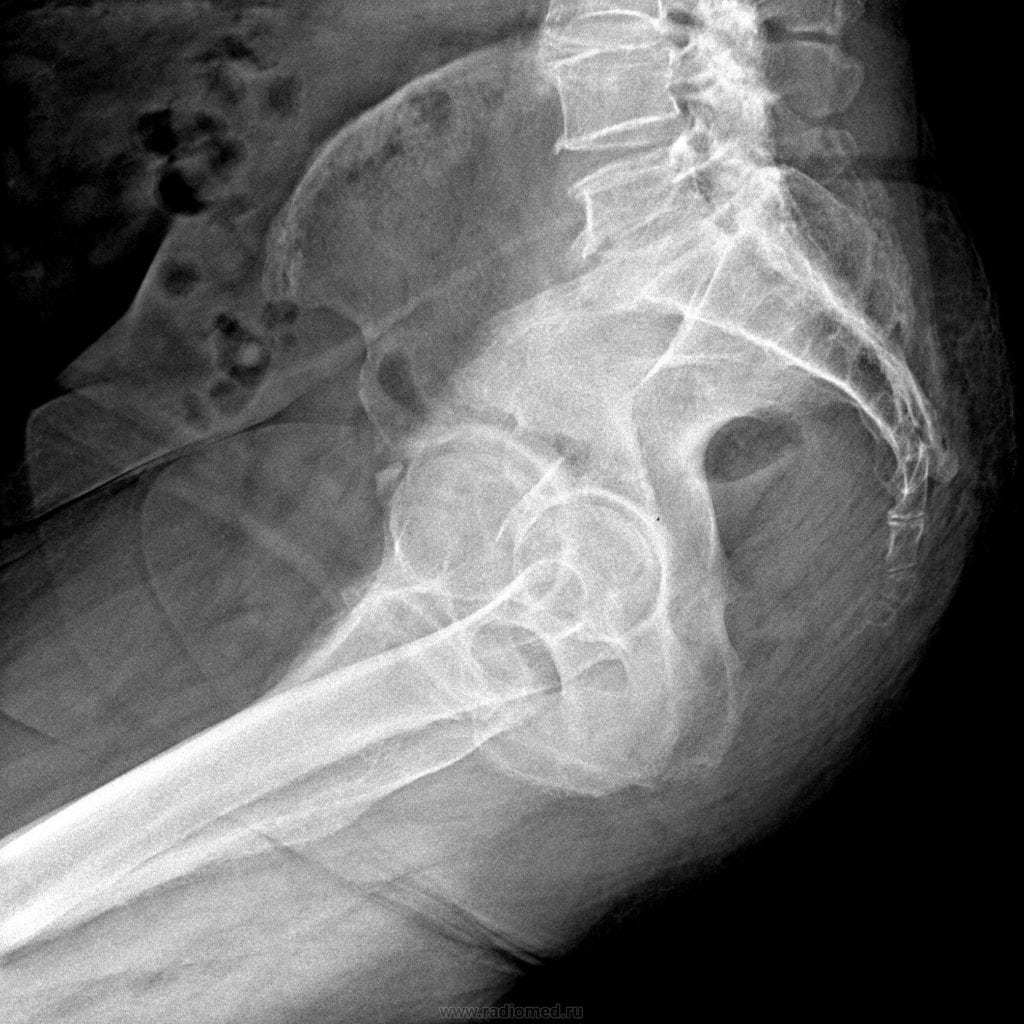

- Обязательно сделайте рентгенографию копчиковой кости и крестца;

Рентген

Исследование помогает выявить причины, приведшие к болезненности копчика. С помощью рентгенографии можно диагностировать поясничный остеохондроз, межпозвоночную грыжу, спондилолистез. Процедура позволяет установить также стадию заболевания, степень поражения тканей, количество возникших осложнений.

Рентген копчика.